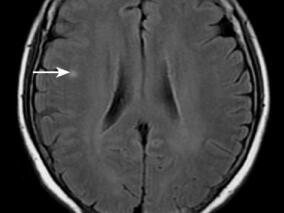

1小时条评论1 病例简介 患者女,25岁,蒙古族,以突发右侧肢体无力1个月余于2008年6月10日收入院。患者主诉于入院前1个月余午睡后出现右腿麻木,无明显无力,未在意,次日晨起时发觉右侧肢体麻木加重,自觉没有知觉,伴有右侧肢体无力,易摔倒,需要人扶持方能行走,无头痛头...